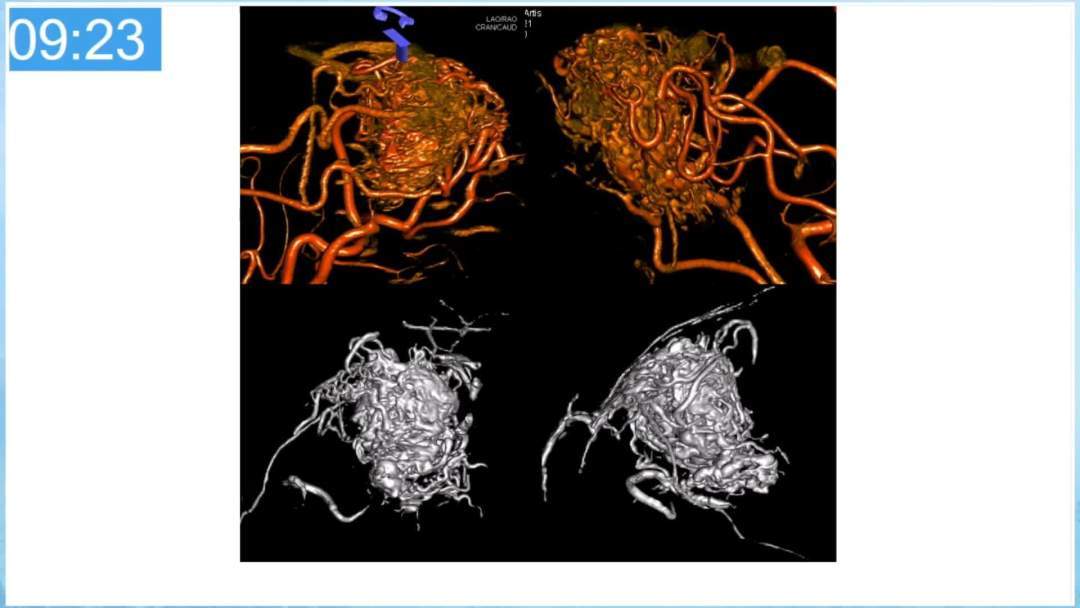

本期为大家特别分享:空军军医大学唐都医院邓剑平教授的精彩会议内容《颅内动静脉畸形的复合手术治疗》,欢迎大家阅读和分享!

合理的复合平台下的综合治疗,针对每一个病变对应不同方法安全性分析,不预设、不排斥,每种技术发挥到最佳,互相保障。